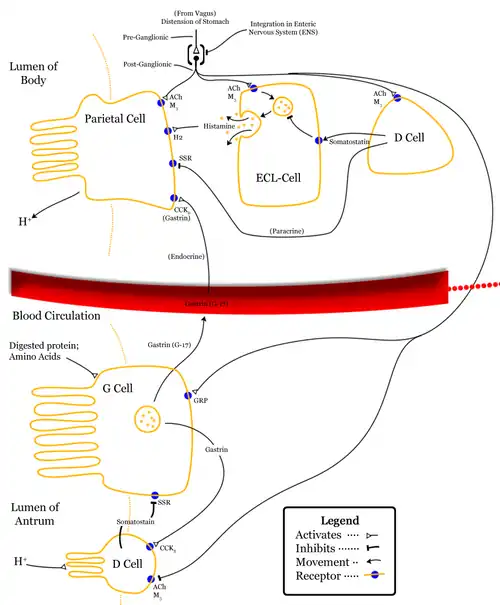

- Parietal cells ("parietal" means "relating to a wall"), also known as oxyntic cells are most numerous on the side walls of the gastric glands. The parietal cells secrete hydrochloric acid (gastric acid). This needs to be readily available for the stomach in a plentiful supply, and so from their positions in the walls, their secretory networks of fine channels called canaliculi can project and ingress into all the regions of the gastric-pit lumen. Another important secretion of the parietal cells is intrinsic factor. Intrinsic factor is a glycoprotein essential for the absorption of vitamin B12.[1] The parietal cells also produce and release bicarbonate ions in response to histamine release from the nearby ECLs, and so serve a crucial role in the pH buffering system.[11]

- Enteroendocrine cells – They are usually present in the basal parts of the gastric glands, which is differentiated into three cell types – enterochromaffin like cells (ECL cells), G cells, and D cells.

- Enterochromaffin-like cells (ECL cells) – They release serotonin and histamine. These cells store and release histamine when the pH of the stomach becomes too high. The release of histamine is stimulated by the secretion of gastrin from the G cells.[1] Histamine promotes the production and release of HCL from the parietal cells to the blood and protons to the stomach lumen. When the stomach pH decreases (becomes more acidic), the ECLs stop releasing histamine.

- G cells – They secrete gastrin hormone. Gastrin stimulates the gastric glands to release gastric acid. These cells are mostly found in pyloric glands in the pyloric antrum; some are found in the duodenum and other tissues. The gastric pits of these glands are much deeper than the others and here the gastrin is secreted into the bloodstream not the lumen.[12]

- D cells – D cells secrete somatostatin. Somatostatin suppresses the release of hormones from the digestive tract.

Layers of stomach wall Gastric acid regulation